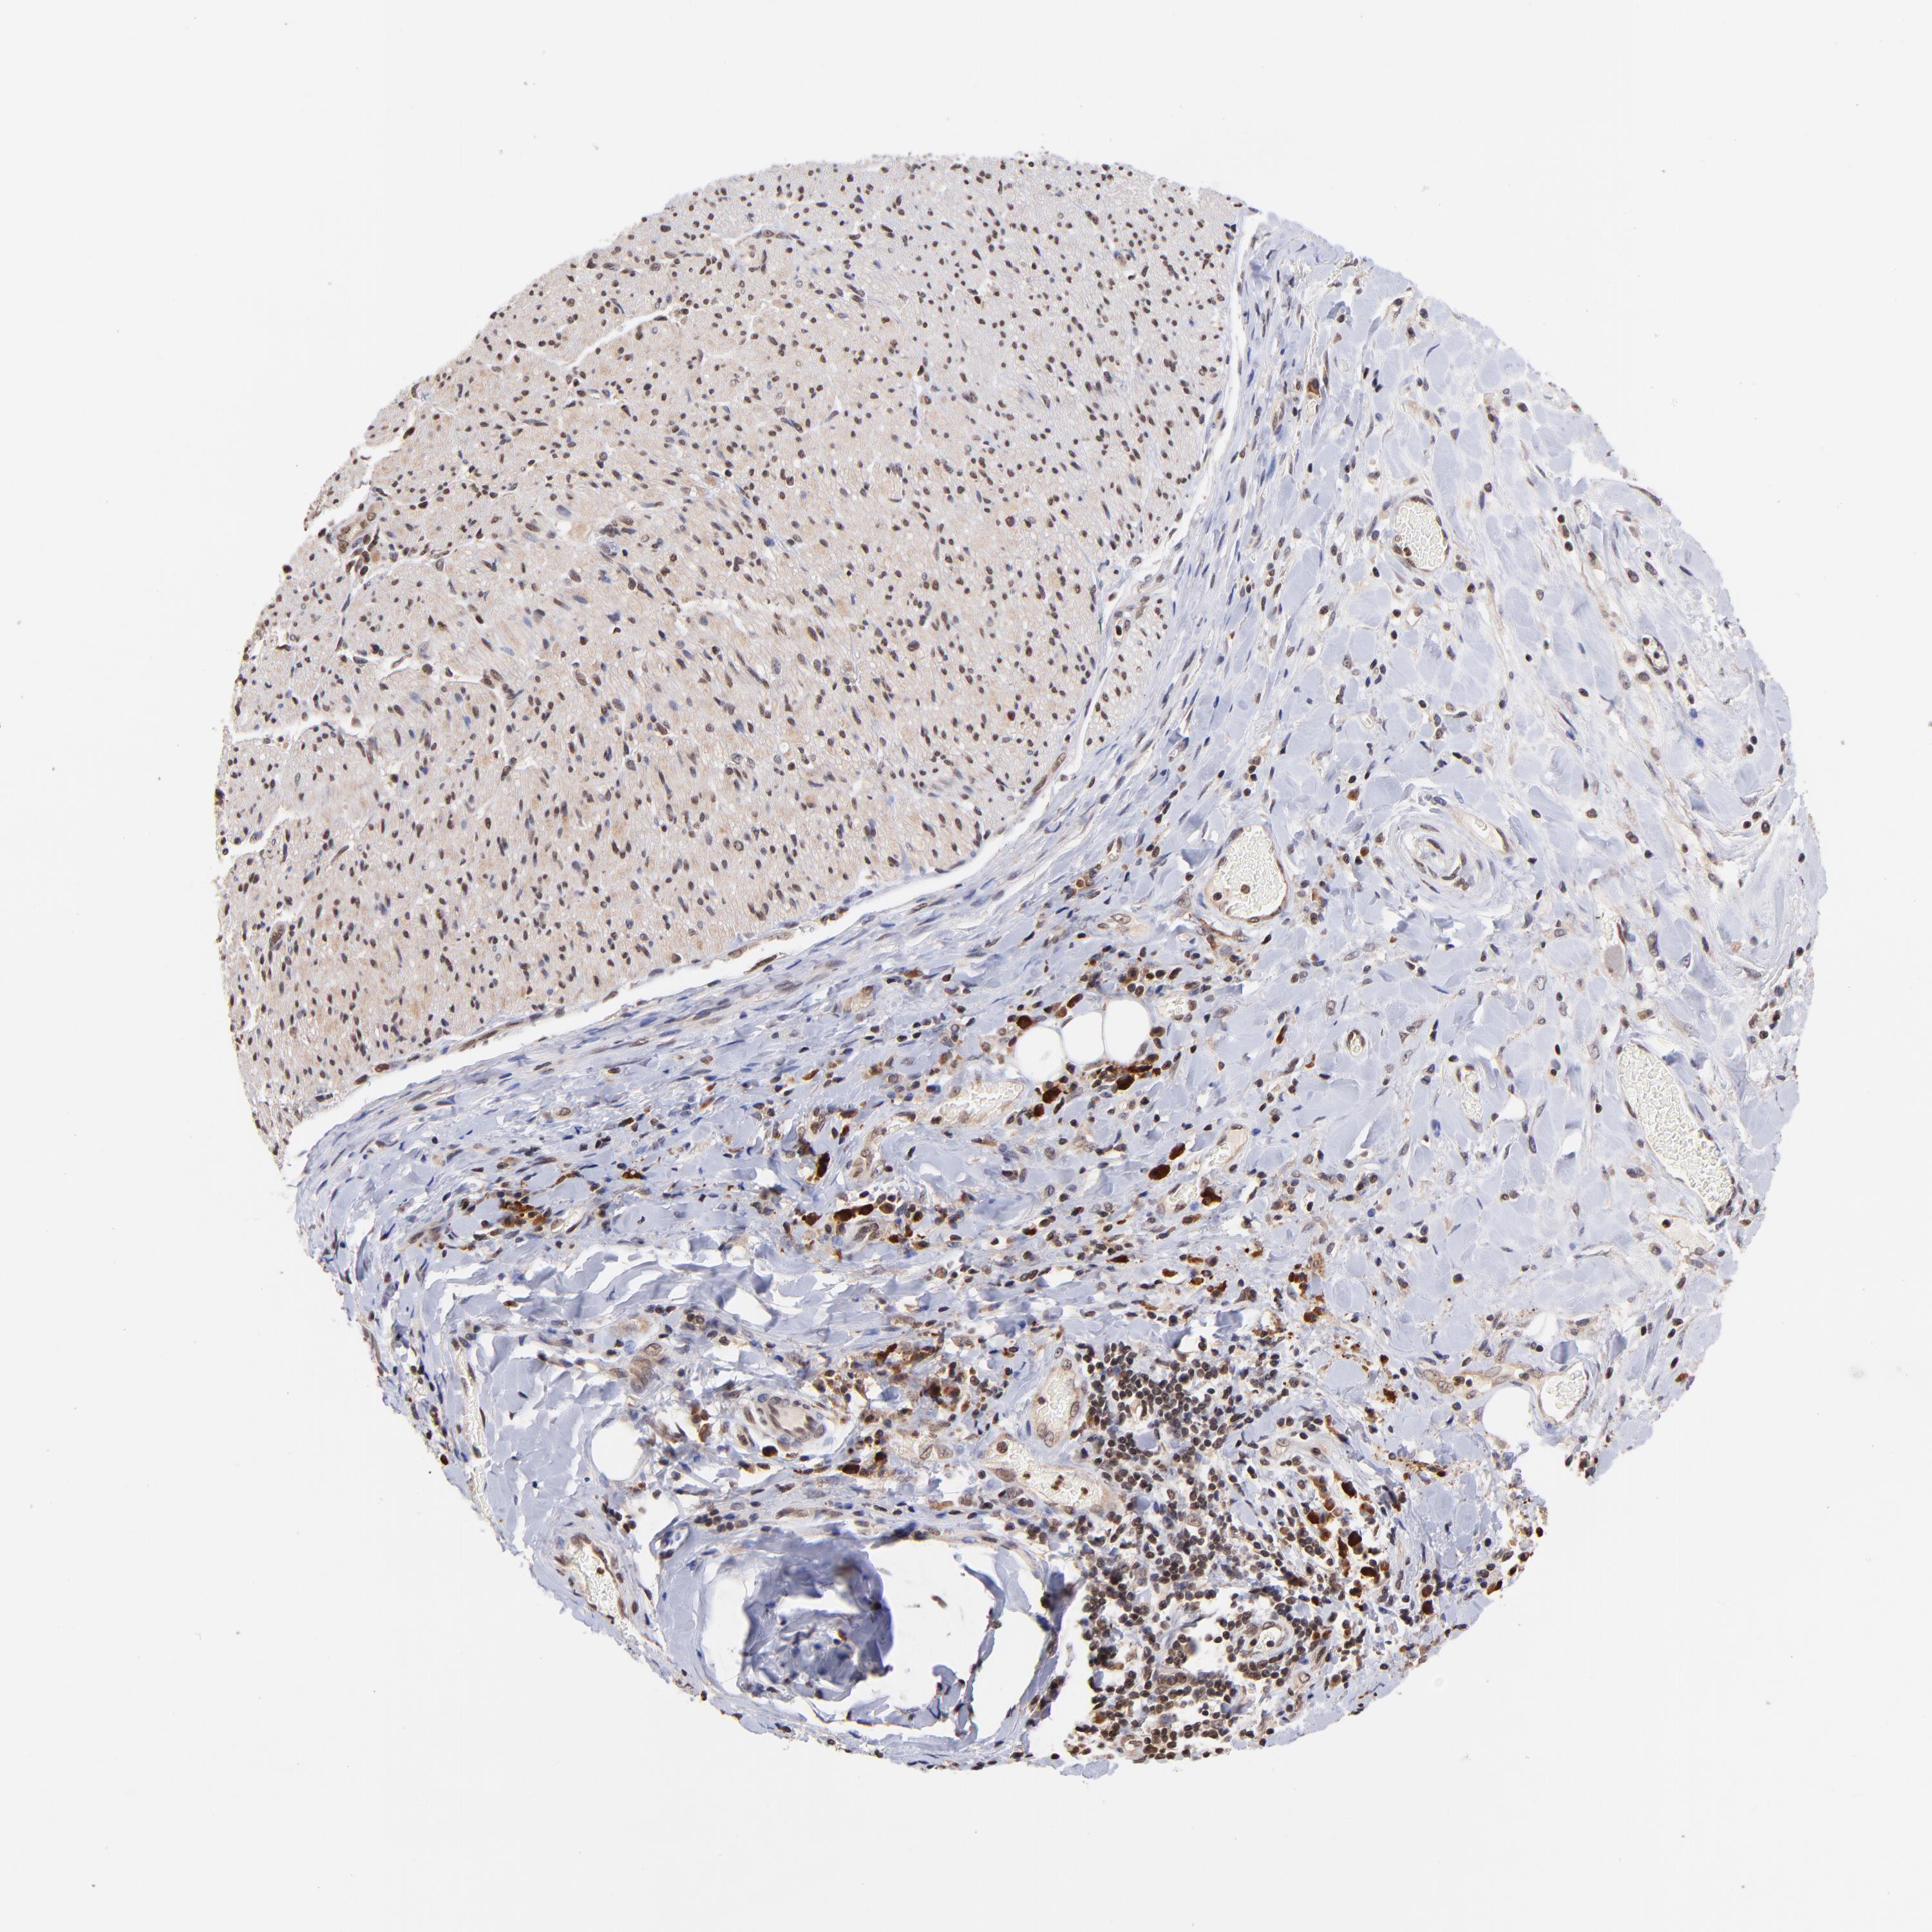

LIVER CANCER - Protein expressioni

A mouse-over function shows sample information and annotation data. Click on an image to view it in a full screen mode. Samples can be filtered based on level of antibody staining by selecting one or several of the following categories: high, medium, low and not detected. The assay and annotation is described here.

Note that samples used for immunohistochemistry by the Human Protein Atlas do not correspond to samples in the TCGA dataset.

Antibody stainingi

Antibody staining in the annotated cell types in the current human tissue is reported as not detected, low, medium, or high, based on conventional immunohistochemistry profiling in selected tissues. This score is based on the combination of the staining intensity and fraction of stained cells.

Each image is clickable and will lead to virtual microscopy that enables deeper exploration of all samples and also displays staining intensity scores, fraction scores and subcellular localization as well as patient and tissue information for each sample.

Antibody HPA003113

Staining

High

Medium

Low

Not detected

Intensity

Strong

Moderate

Weak

Negative

Quantity

>75%

75%-25%

<25%

None

Location

Nuclear

Cytoplasmic/membranous

Cytoplasmic/membranous,nuclear

Carcinoma, Hepatocellular, NOS

Cholangiocarcinoma